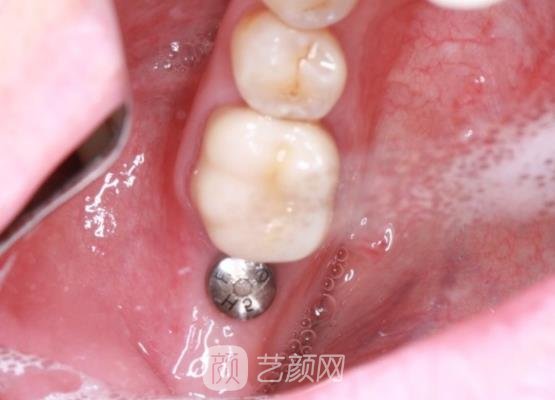

所以手术大概用了五六个月的时间就恢复了,现在我的牙齿又重新长出来了,看到牙齿又重新长出来,我又能够吃一些好吃的东西了,而且用手抚摸了一下牙齿,也没有那种松动的感觉。